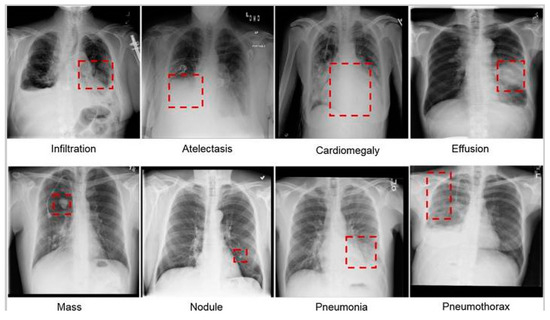

The different types of lung infections. Eight of the most common lung diseases; namely, infiltration, atelectasis, cardiac hypertrophy, effusion, lumps, nodules, pneumonia, and pneumothorax; observed in the chest radiographs referred in Figure 2. A reliable automated detection system should perform well on above infection, abnormalities and generalise effectively to detect previously unseen or rare abnormalities. Adapting and identifying new patterns and abnormalities is crucial for the system’s practical utility [40]. Developing algorithms that can learn from limited labelled data and generalise well to unseen cases is a significant challenge in the field of automated chest X-ray analysis [41].

Figure 2.

The different types of lung infections. Eight of the most common lung diseases; namely, infiltration, atelectasis, cardiac hypertrophy, effusion, lumps, nodules, pneumonia, and pneumothorax; observed in the chest radiographs [12].